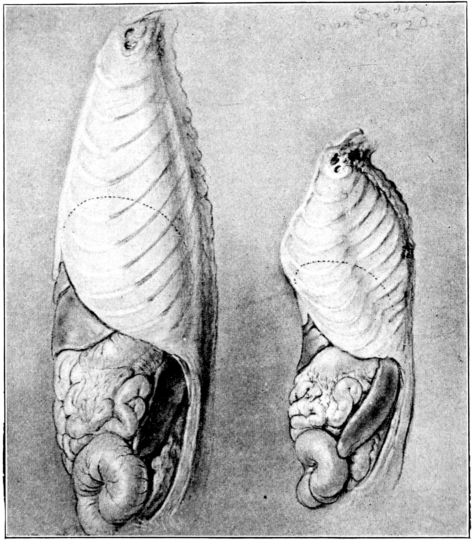

| 142. | Chest walls of normal and rachitic rats of the same age | 383 |

| 143. | Interior of specimens in Fig. 142 | 384 |